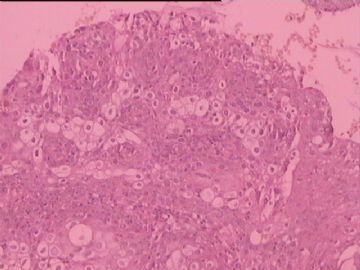

糜烂

图2